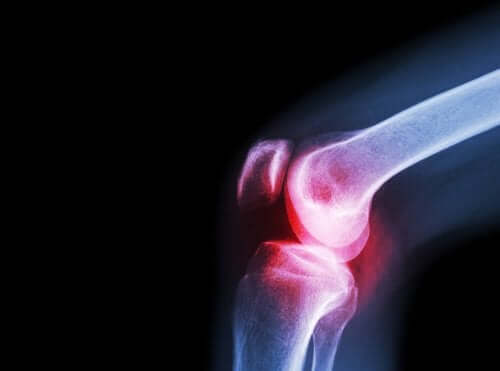

En outre, on peut réaliser une radiographie de l’articulation qui pose problème. Les rayons X et d’autres méthodes d’imagerie médicale peuvent aider à évaluer les dommages.